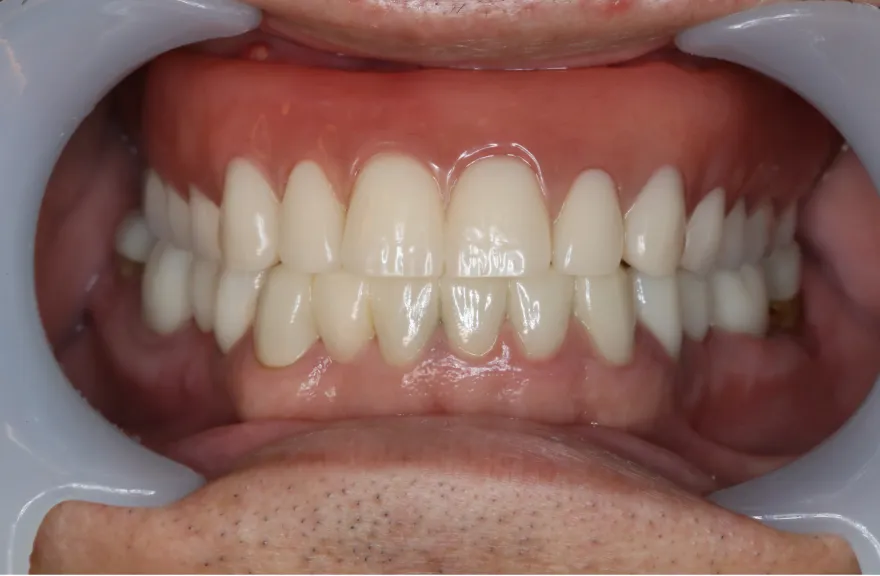

【治療例 2】金属を白くしたい63歳

写真の通りに治療を終了いたしました。

各所虫歯に侵食されていましたが、歯を残すことができたのでインプラントの数をおさえることができました。

下の前歯が先天的に1本欠損しており、そのため噛み合わせを構築することが難しいケースでした。矯正治療を併用することで前歯と奥歯をバランスよく噛ませることに成功しました。